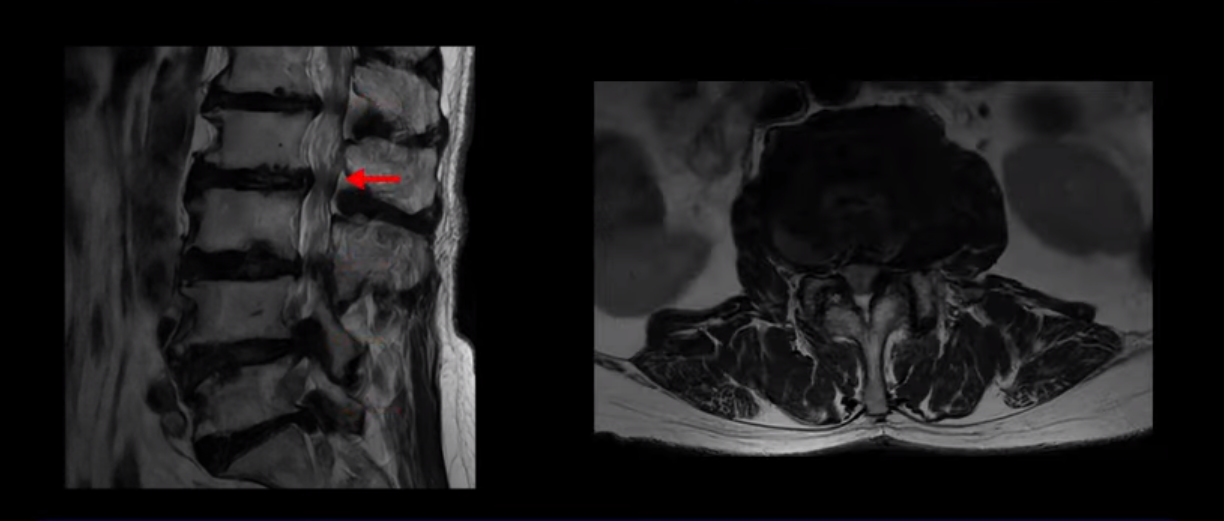

이 환자분은 MRI로 보면 허리 여러 마디가 신경이 매우 심하게 눌려 보이는 분입니다. 이분 MRI를 보면서 간단히 설명해 드린 후 어떻게 이렇게 신경이 심하게 눌린 환자분이 수술 없이 근육신경재활치료로 좋아질 수 있는지, 다리가 아파 걷지 못하는 환자가 어떻게 안 아프고 잘 걸을 수 있게 되는지, 10년 동안 괴로웠던 양 발의 시린 증상은 어떻게 사라질 수 있는지, 치료는 어떻게 하는지 자세히 설명 드리겠습니다.

MRI 보시면 (2-8) 허리의 5마디가 전부 다 심하게 퇴행되어 있습니다.

5마디 전부 다 심한 중심성 협착이 있습니다.

1번 2번,

2번 3번,

3번 4번,

4번 5번,

5번 6번

이렇게 모두 다 심하게 막히는 경우는 드문데요. 또한 오른쪽, 왼쪽 신경이 빠져나가는 추간공도 다 심하게 막혀있습니다.

오른쪽, 왼쪽 이렇게 신경 구멍들이 다 좁아지고 신경이 눌리니까 양쪽 다리가 발바닥까지 아파서 걷기 어렵고 양쪽 발이 10년 넘게 시린 겁니다. 당연히 수술해서 눌린 신경을 풀어줘야 한다고 들으셨는데요. 이런 환자분을 어떻게 수술 없이 치료할까요? 지금부터 설명해 드립니다.